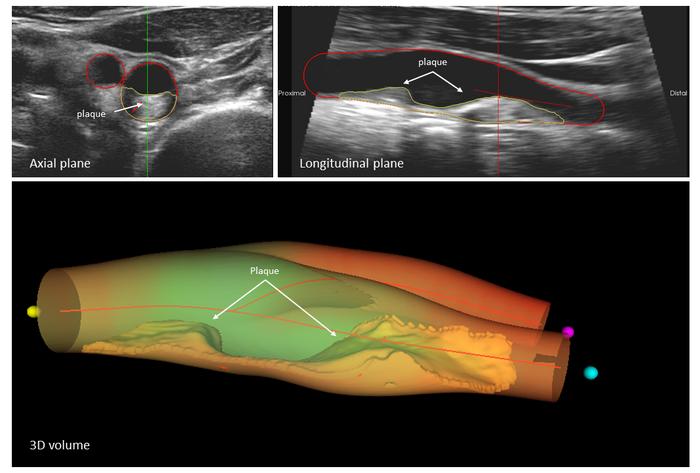

BioImage, led by Dr. Fuster, was the first study to demonstrate the value of 3D echocardiography and other advanced imaging technologies to detect atherosclerotic disease of the large vessels long before the appearance of symptoms. “The long asymptomatic phase of the disease presents a window of opportunity that has not been exploited in the younger population,” said Fuster, who is the lead author on the JACC study.

The study participants were examined with two imaging techniques. The burden of atherosclerotic plaques in the carotid arteries was measured with vascular ultrasound, which allows detailed visualization of the interior of blood vessels, and calcification of the coronary arteries was assessed by computed tomography. Joint first author Dr. Ana García Álvarez, a CNIC group leader and head of the cardiology service at Hospital Clínic in Barcelona, explained that “Carotid plaque is an accumulation of cholesterol, calcium, and other circulating substances that are deposited in the blood vessel wall. The formation of these plaques can narrow or block the carotid arteries, reducing blood flow to the brain and increasing the risk of a cerebrovascular accident or stroke.”